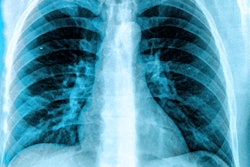

Reveal 35C includes KA Imaging's SpectralDR technology, which images bone and soft tissue images with a single standard x-ray exposure, the company said.